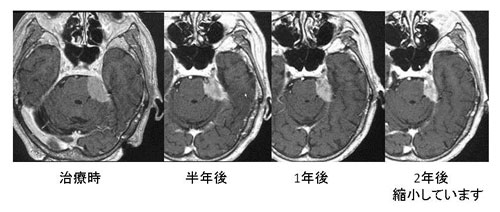

髄膜腫

髄膜腫の治療の第一選択は手術です。何らかの理由で手術が不可能な方や腫瘍の発生した部位が手術困難な場合にガンマナイフの適応になります。ガンマナイフ治療の目標は、腫瘍の発育を停止させ、これ以上神経症状が進まないことを治療目標としています。ガンマナイフ後髄膜腫の成長が停止する確率は一般に10年間で90%です。手術後の残存腫瘍、手術が難しい頭蓋底(海綿静脈洞部や斜台部など)や脳の深部の腫瘍、高齢者や手術に耐えられない状態で、腫瘍の最大径が2.5~3cm以下の場合が非常に良い適応です。